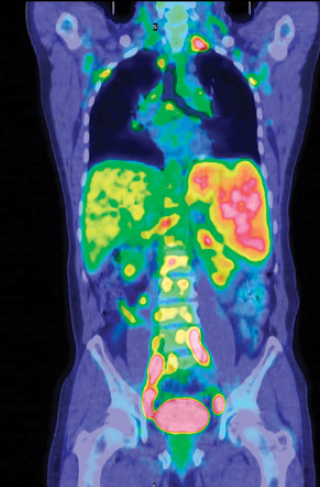

套细胞淋巴瘤(MCL)是一种罕见的侵袭性非霍奇金淋巴瘤,多发于老年人。较年轻的患者可使用免疫化疗联合自体干细胞移植作为标准一线治疗方法。虽然很大一部分患者会发生初始缓解,但大多会复发并且对后续的免疫化疗反应较差,并且通常会死于疾病进展。

Michael Wang及其同事在《The Lancet Oncology》初次报道了利妥昔单抗联合依鲁替尼治疗复发MCL的结果。该项单中心2期试验中,50名患者接受了该联合治疗方法治疗。与依鲁替尼单药治疗MCL结果相比,该联合治疗方法产生的客观缓解率(88% vs 68%)和完全缓解率(68% vs 21%)均明显升高。另外,该联合治疗方法也缓解了淋巴细胞增多症。较常见的不良反应主要为1-2级(包括恶心、腹泻、疲乏),但与依鲁替尼单药试验相比,发生率却明显增加。更重要的是,该联合治疗方法似乎对血液学毒性影响不大,但3-4级不良反应和治疗中止相关不良反应的发生率相对减小。

依鲁替尼是一个MCL治疗的重大进展,利妥昔单抗联合依鲁替尼明显提高了效果。毒性反应发生率略微增加,所以有必要进行更长期的随访来明确已达到的缓解能否持续下去。接下来,需要向无化疗方案转化,尤其是那些效果佳、可耐受的治疗方法。然而,一线免疫化疗仍对很多患者有效,并且依鲁替尼可作为大多数患者复发的挽救治疗。在将来,仍需进一步对该联合治疗方法进行研究。另外,EudraCT研究对比了依鲁替尼联合利妥昔单抗与标准免疫化疗分别一线治疗年老MCL的效果,并且将会为我们证实该联合治疗方法可否作为MCL的新标准方案。